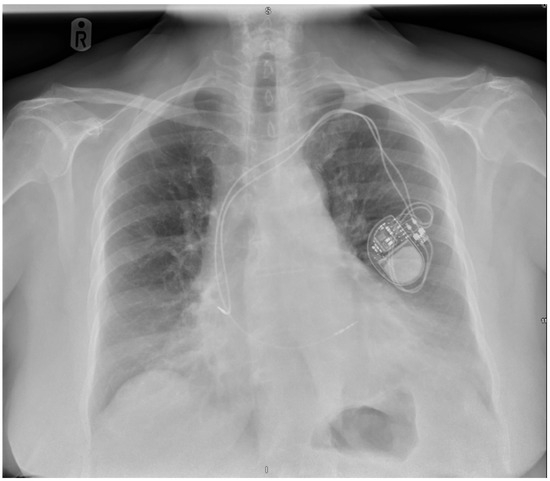

Background/Objectives: Twiddler’s syndrome is an uncommon but clinically important complication of implantable cardiac devices, in which generator rotation within the pocket results in lead torsion, lead retraction, and device malfunction. Recurrence can necessitate repeated surgical intervention and may be preventable through early risk

Background/Objectives: Twiddler’s syndrome is an uncommon but clinically important complication of implantable cardiac devices, in which generator rotation within the pocket results in lead torsion, lead retraction, and device malfunction. Recurrence can necessitate repeated surgical intervention and may be preventable through early risk identification and procedural strategies. Methods: We describe a single-centre case series of three female patients with pacemaker-associated Twiddler’s syndrome. Clinical presentation, timing of lead retraction, management strategies (including pocket location and fixation approach), recurrence, and follow-up outcomes were reviewed. Results: All patients were older women and developed symptomatic device failure early after implantation, with radiographic confirmation of lead retraction and coiling occurring within three weeks in all cases. Recurrence was observed when enhanced preventive measures were not employed. Notably, in one patient, recurrence occurred after an initial revision in a second prepectoral pocket, prompting subsequent reimplantation in a subpectoral location with reinforced fixation and structured patient and family counselling, after which no further recurrence occurred at one year. In the remaining cases, revision with reinforced generator fixation and counselling was associated with stable lead position and satisfactory device function during follow-up. Conclusions: Twiddler’s syndrome most commonly presents in the first weeks following implantation. Proactive identification of at-risk patients and consideration of reinforced fixation and pocket strategies at the index procedure may reduce recurrence and avoid repeat interventions.

Figure 1